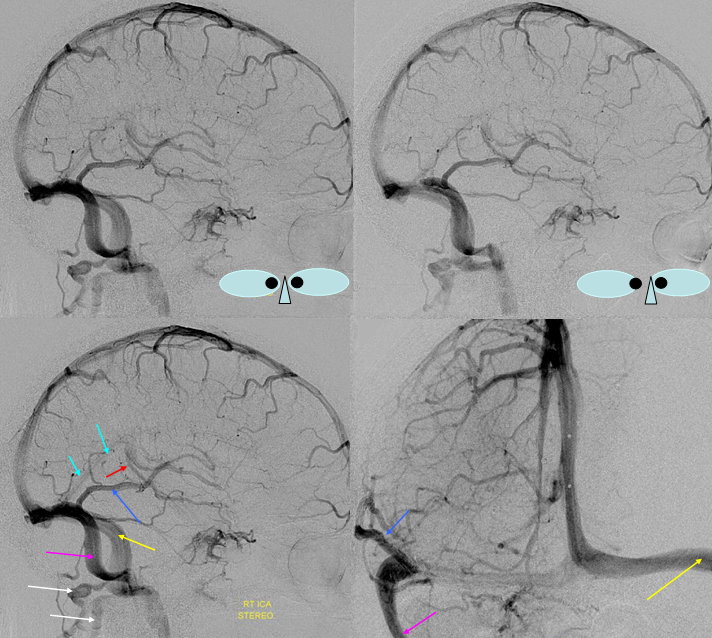

Following embolization, resection, recurrence (as frequently the case with childhood AVMs) and gamma-knife, things look good. Stereo, of course.

Following embolization, resection, recurrence (as frequently the case with childhood AVMs) and gamma-knife, things look good. Stereo, of course.